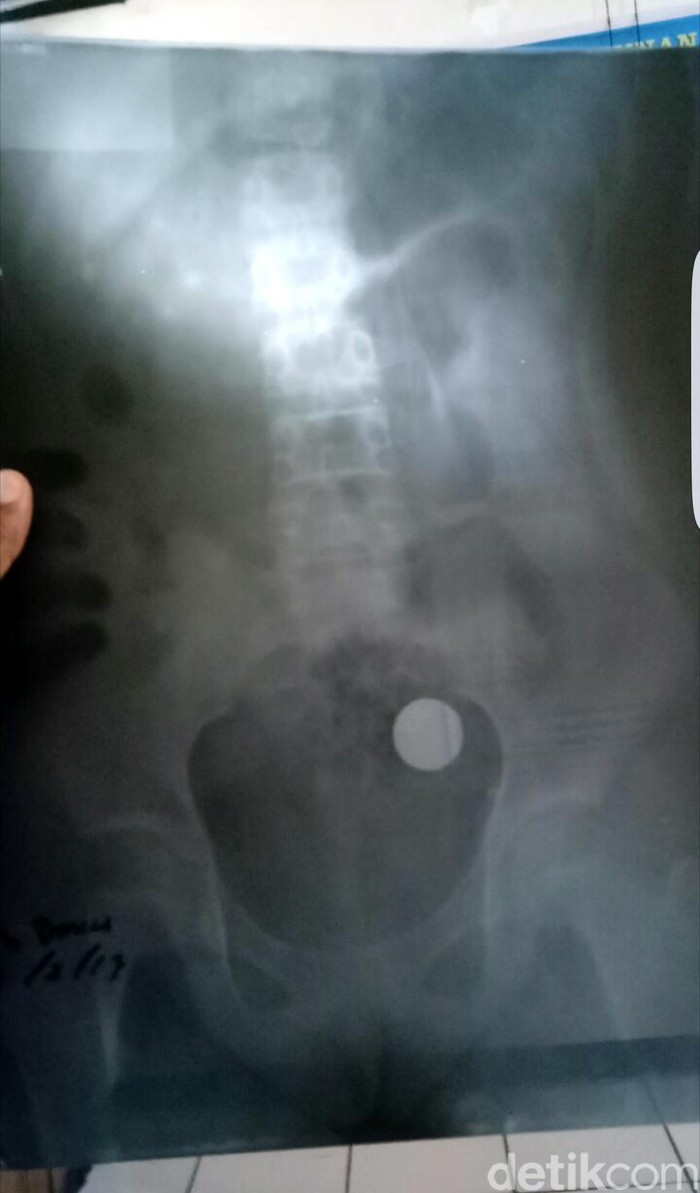

Koin tersebut baru diketahui setelah mereka membawa Danianis ke rumah sakit untuk melakukan pemeriksaan sinar X atau Rontgen. Hasil pemeriksaan diketahui ada sebuah benda membulat menempel di jaringan ususnya.

Pihak rumah sakit yang melakukan Rontgen menyarankan agar Danianis menjalani operasi, karena kondisi koin yang sudah mengeluarkan semacam racun harus segera diangkat.